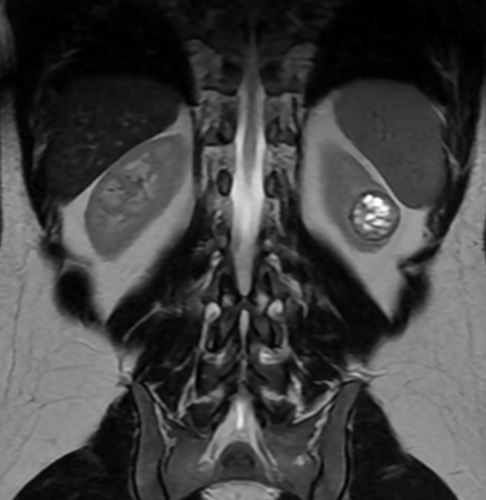

O tumor é agressivo, tem alta complexidade (RENAL score 9p) e está localizado muito próximo das vias urinárias, com risco de comprometer completamente meu rim.A única forma de me tratar com segurança e preservar ao máximo minha função renal é por meio de uma cirurgia robótica, um procedimento minimamente invasivo, de alta precisão. Mas infelizmente meu plano de saúde (SulAmérica) não cobre esse tipo de cirurgia.